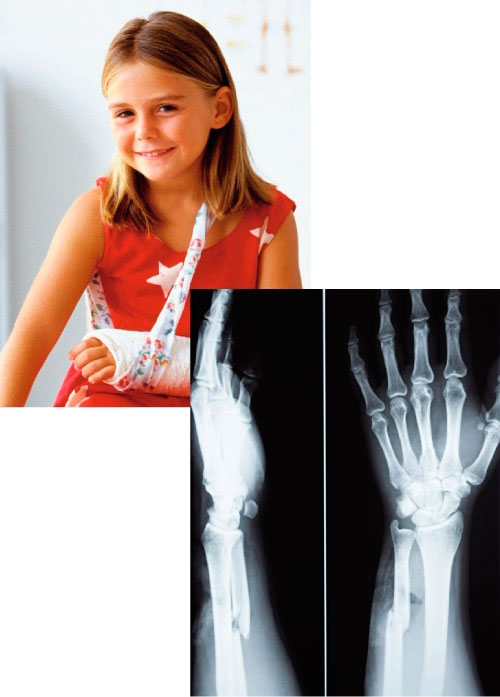

Hasta finales del siglo xix no existía ninguna otra forma de observar el interior del cuerpo humano que no fuese abrir el cuerpo del paciente.

Pero un físico alemán llamado Wilhelm Roentgen realizó un descubrimiento que lo cambió todo. En el año 1895, mientras trabajaba en su laboratorio, descubrió los rayos X. Estos rayos atraviesan fácilmente la materia y permiten obtener una imagen del cuerpo que traspasan.

Roentgen pidió a su mujer que colaborase con él en el experimento. Expuso su mano a la acción de los rayos X y pudo observar por primera vez los huesos de una persona viva. ¡Había obtenido la primera imagen del interior del cuerpo humano!

En 1901 recibió el primer Premio Nobel de Física por su notable descubrimiento.

Actualmente esta técnica nos ofrece información del interior del cuerpo, proporcionando imágenes que sirven para conocer mejor la anatomía humana y también para detectar lesiones y enfermedades.

• Las fracturas. Se producen por la rotura de un hueso, que puede partirse o astillarse. El tratamiento más habitual consiste en colocar una escayola o una tablilla que mantiene el hueso en la posición correcta hasta que se repara. Si la fractura es complicada, se pueden colocar clavos o placas metálicas.

Interpretar radiografías

Las radiografías nos proporcionan imágenes del interior de nuestro cuerpo. Así podemos observarlo mejor y detectar lesiones o enfermedades. Aprende cómo se interpretan.